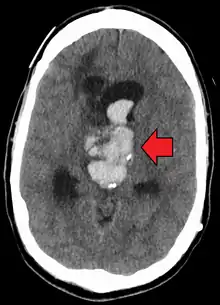

| Axial CT scan of a spontaneous intracranial hemorrhage | |

CT scan (computed tomography) is the definitive tool for accurate diagnosis of an intracranial hemorrhage. In difficult cases, a 3T-MRI scan can also be used.